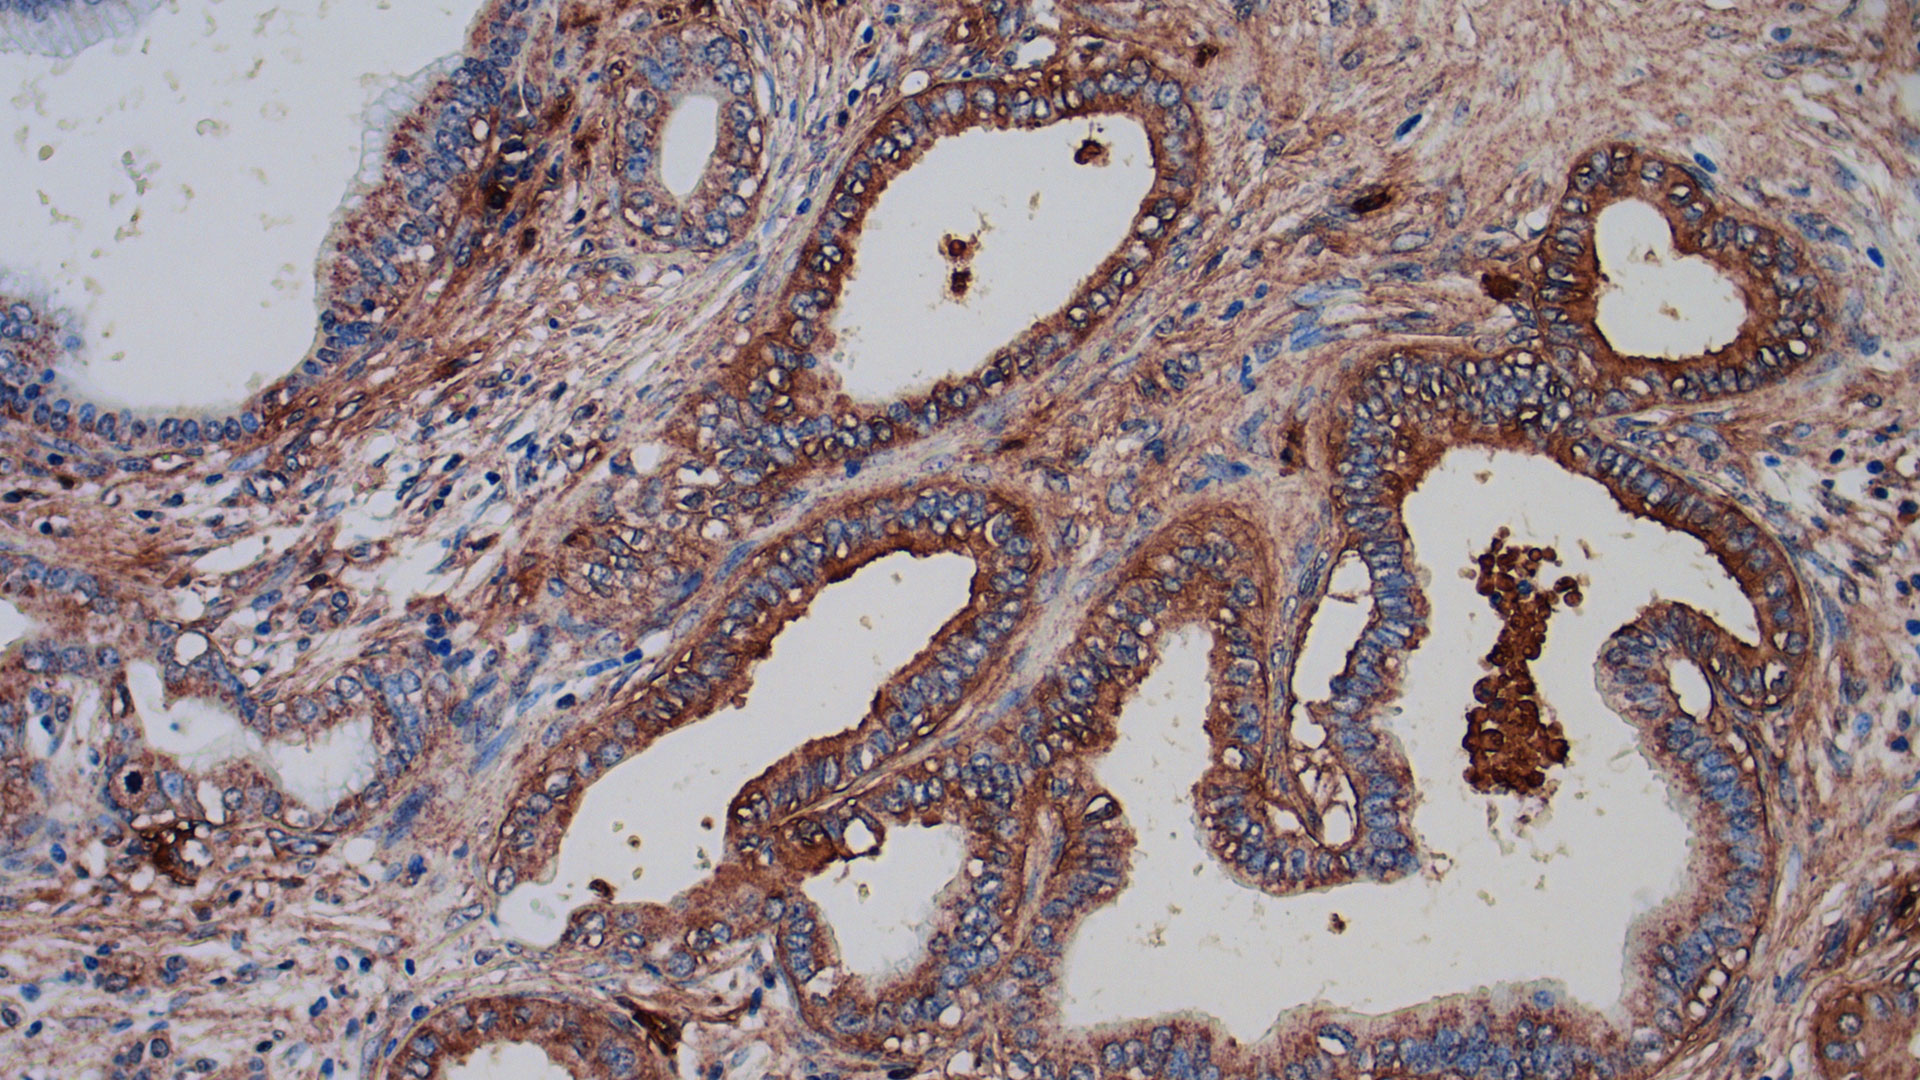

Immunohistochemical staining of an SRI molecular guidance system in human pancreatic tissue.